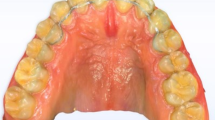

Group I (study group): Twenty preschool children used a modified fixed bridge in their anterior extraction site. (Fig1, 2, 3)

Premature loss of upper ant teeth.

Rehabilitation of extraction site with modified fixed bridge.

Palatal view of modified fixed bridge.